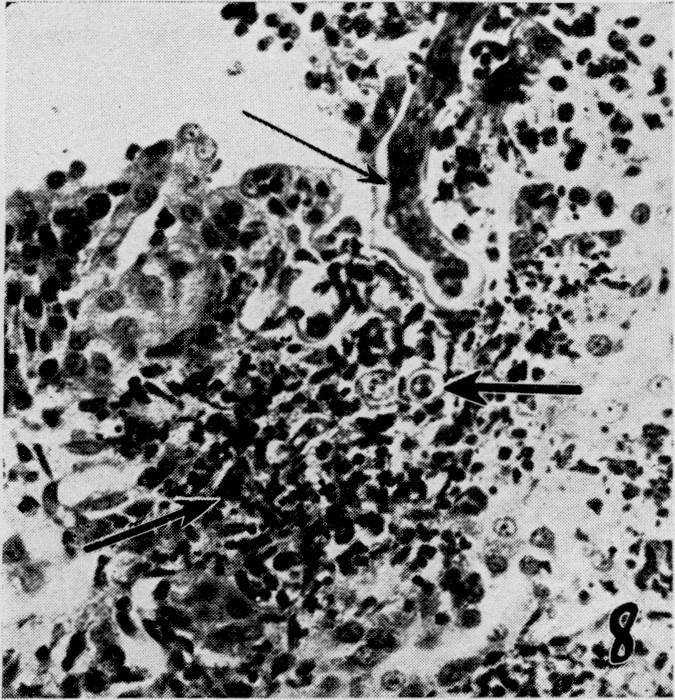

The effects of metabolic alterations on experimental Rhizopus oryzae (mucormycosis) infection.

Yale J Biol Med. 1956 Sep;29(1):23-32.